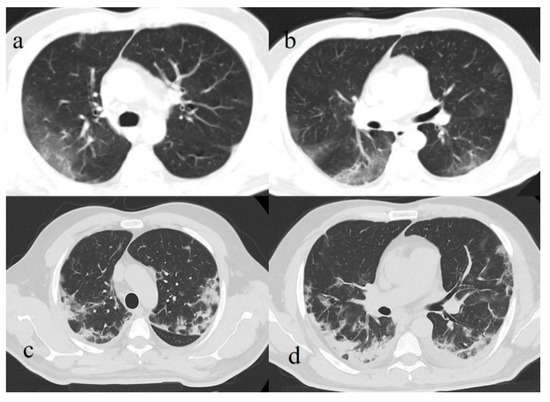

- Li, K.; Fang, Y.; Li, W.; Pan, C.; Qin, P.; Zhong, Y.; Liu, X.; Huang, M.; Liao, Y.; Li, S. CT image visual quantitative evaluation and clinical classification of coronavirus disease (COVID-19). Eur. Radiol. 2020, 30, 4407–4416. [Google Scholar] [CrossRef] [PubMed] [Green Version]

- Wang, Y.; Dong, C.; Hu, Y.; Li, C.; Ren, Q.; Zhang, X.; Shi, H.; Zhou, M. Temporal Changes of CT Findings in 90 Patients with COVID-19 Pneumonia: A Longitudinal Study. Radiology 2020, 296, E55–E64. [Google Scholar] [CrossRef] [Green Version]